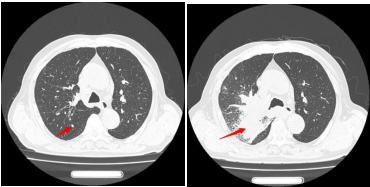

患者王大爷一年前体检发现右肺上叶有一约6×4mm结节,当时未予重视。一年后,他突然出现活动后喘憋症状,复查胸部CT显示右肺上叶后段出现约50×50mm不规则实性团块,影像学高度怀疑肺恶性肿瘤。

经过一个周期的治疗后,患者喘憋、咳嗽等呼吸道症状明显缓解,复查影像显示右肺上叶肿物显著缩小,疗效评估良好。这一结果让患者及家属重拾治疗信心,也为下一阶段治疗奠定了基础。